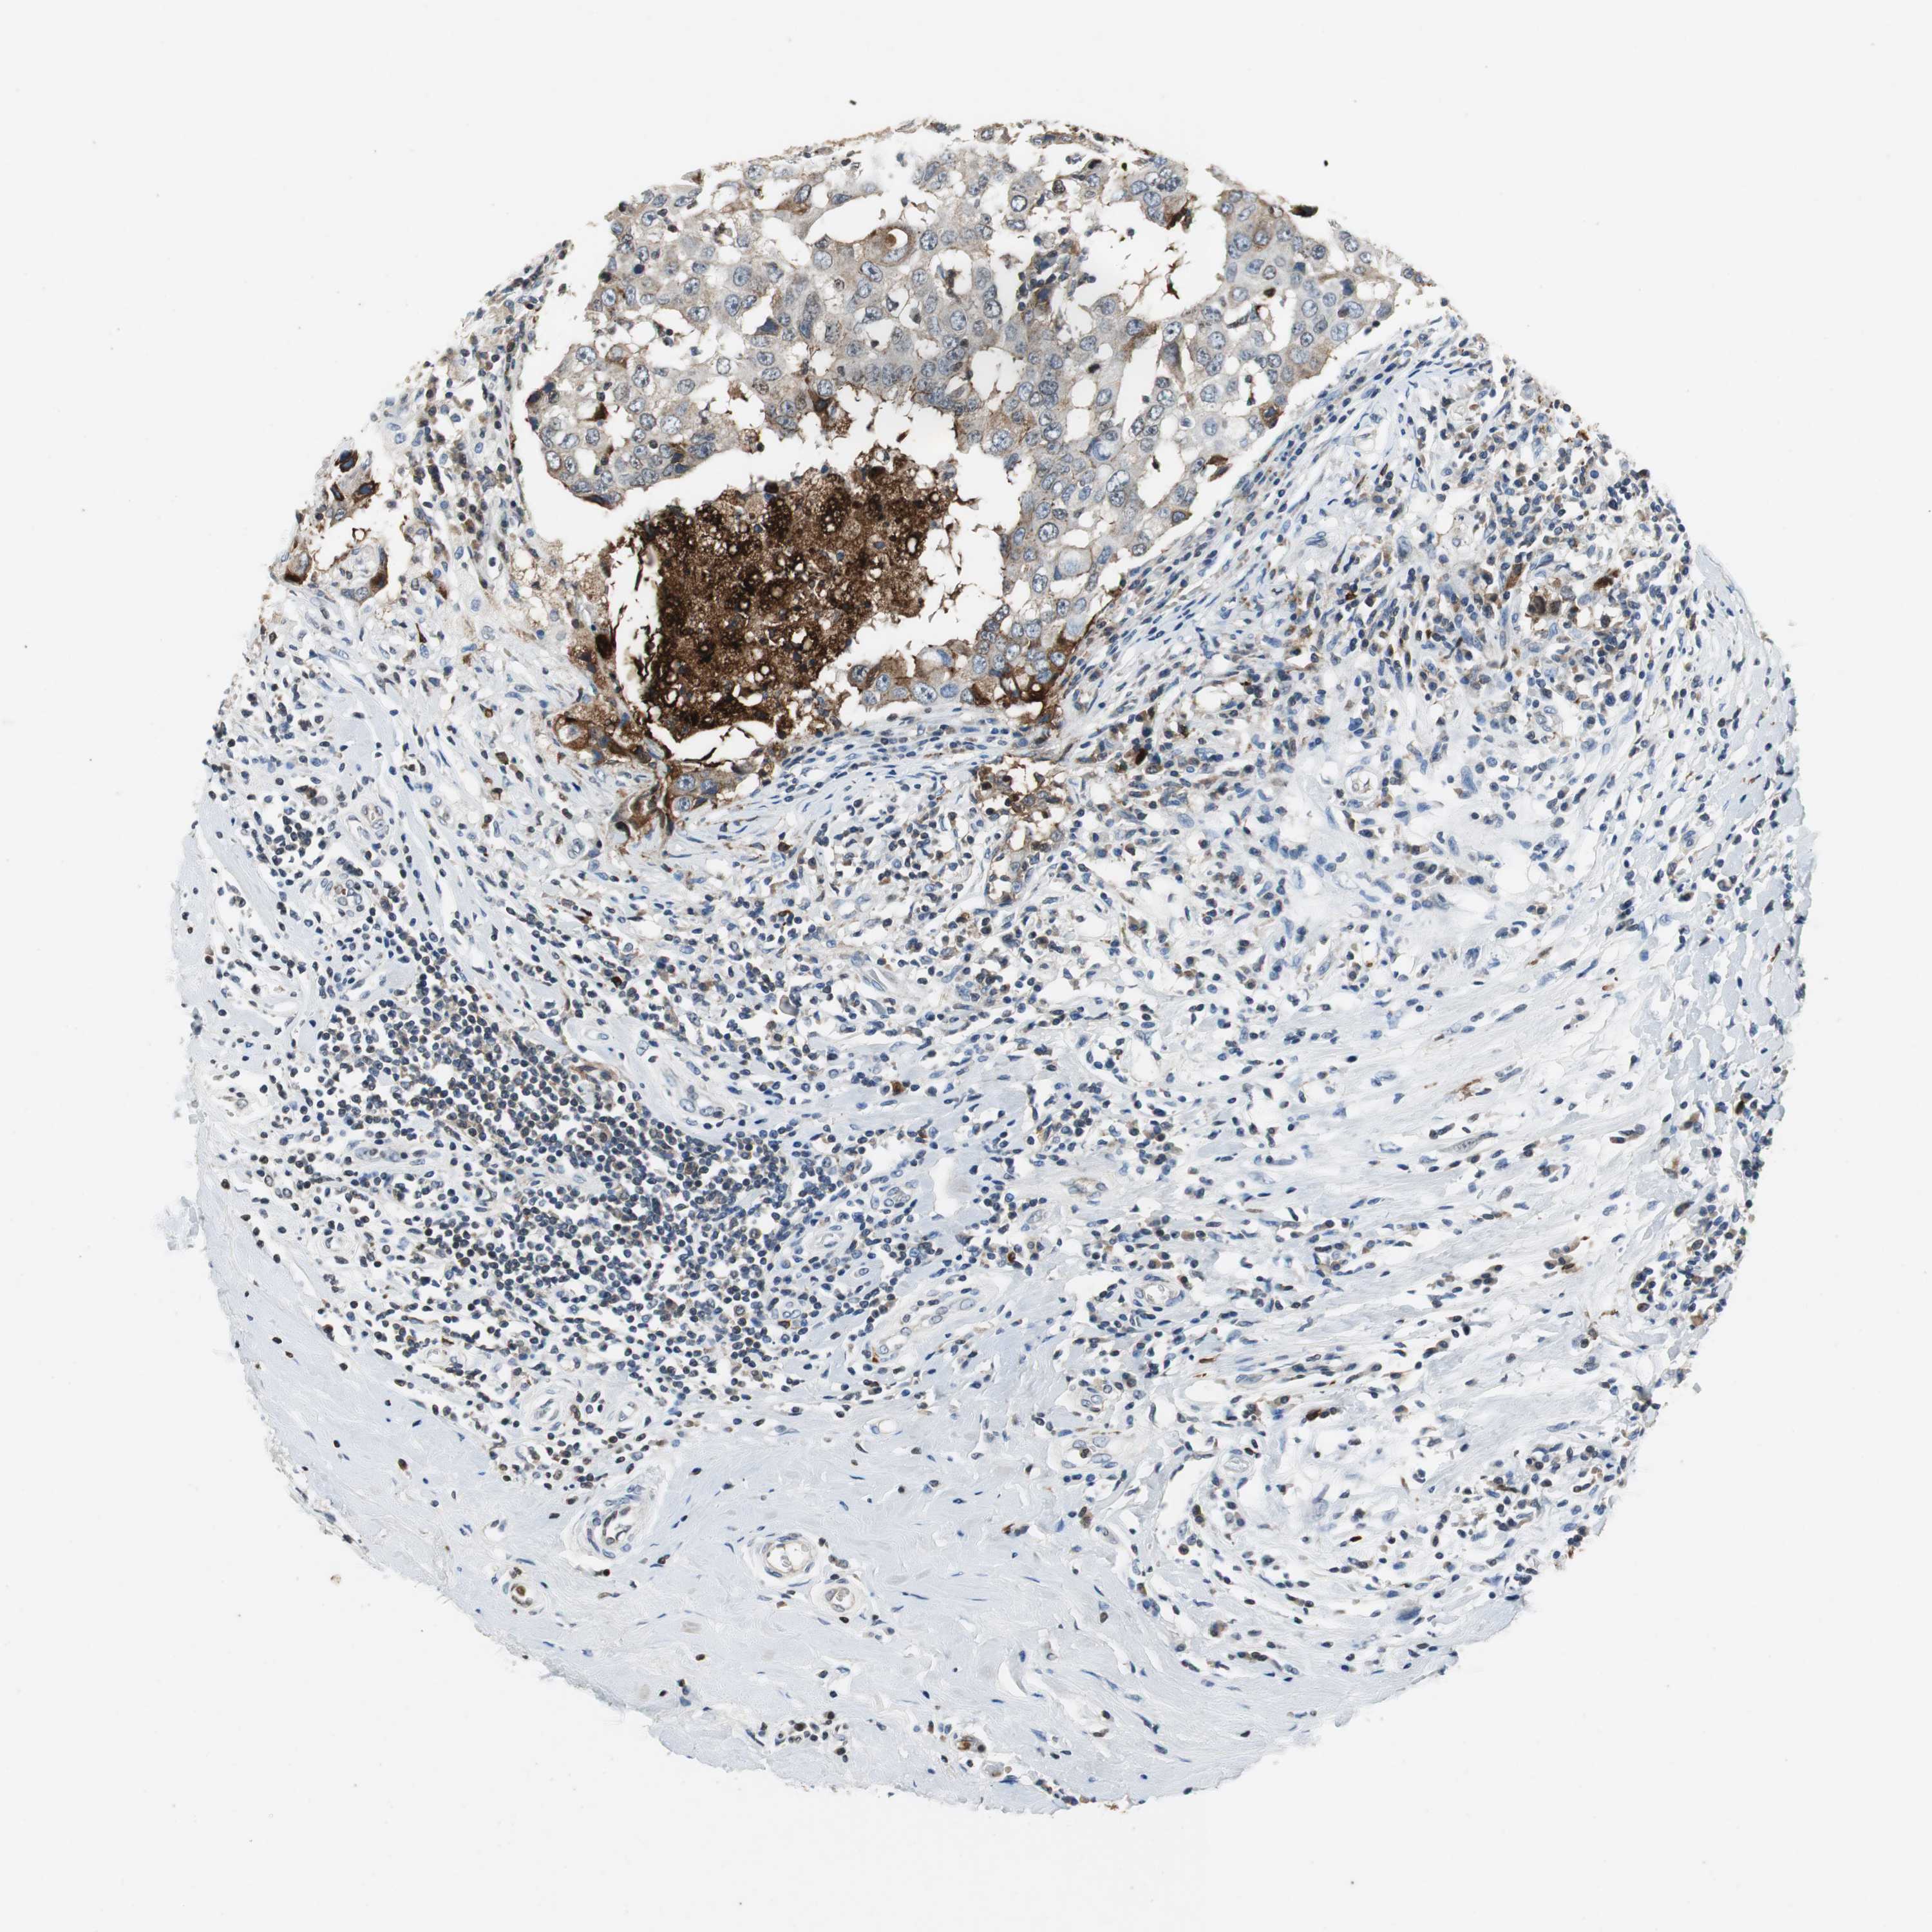

BRCA TCGA BRCA VALIDATION PROTEIN EXPRESSION

ANTIBODIES

AND

VALIDATION